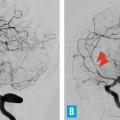

Cet examen reste néanmoins l’exploration artérielle de référence.2 Le risque du cathétérisme est extrêmement faible chez un patient jeune sans athérosclérose ni trouble de la coagulation. Pour que la sensibilité de l’examen soit optimale, l’examen doit être réalisé selon une technique parfaite, avec exploration des quatre axes. L’aspect caractéristique d’une vascularite primitive du système nerveux central associe des rétrécissements artériels segmentaires et étagés avec parfois des dilatations fusiformes interposées, des occlusions distales et des irrégularités pariétales (Explorations extraneurologiques

La présence de rétrécissements segmentaires étagés sur les artères intracrâniennes n’est pas spécifique des vascularites cérébrales : outre le syndrome de vasoconstriction cérébrale réversible déjà évoqué (v . tableau ), il peut s’agir d’emboles multiples en voie de recanalisation (origine cardiaque ou artérielle) ou de sténoses athéromateuses. L’atteinte prédominante sur les artères de gros et de moyen calibre, la présence de facteurs de risque vasculaire et des calcifications sur les parois artérielles à la tomodensitométrie cérébrale sont autant d’arguments en faveur d’une athérosclérose intracrânienne, que l’on rencontre en particulier chez les sujets non caucasiens (africains et asiatiques) et chez les diabétiques.2 En cas de difficulté diagnostique, la répétition des explorations artérielles aide à rattacher des anomalies artérielles à une vascularite, en montrant leurs modifications (amélioration ou aggravation) en quelques semaines.

La présence de rétrécissements segmentaires étagés sur les artères intracrâniennes n’est pas spécifique des vascularites cérébrales : outre le syndrome de vasoconstriction cérébrale réversible déjà évoqué (